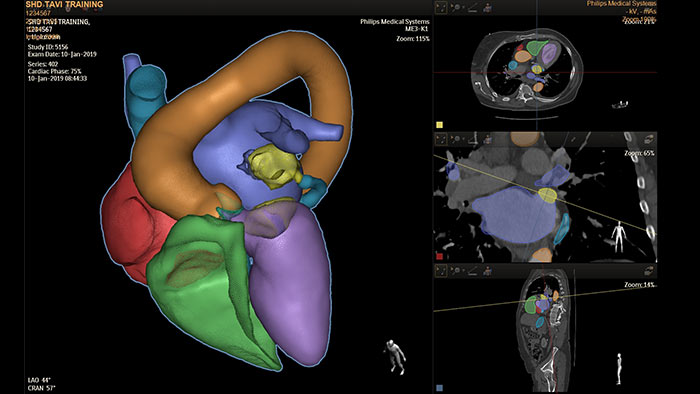

De HeartNavigator is een oplossing voor CT-planning en live overlaygeleiding die gebruikmaakt van automatische hartmodelsegmentatie van de anatomie voor meer gebruiksgemak, een hogere snelheid en een verbeterde reproduceerbaarheid. Bij linkerhartoorsluiting schakelt HeartNavigator het volgende in: